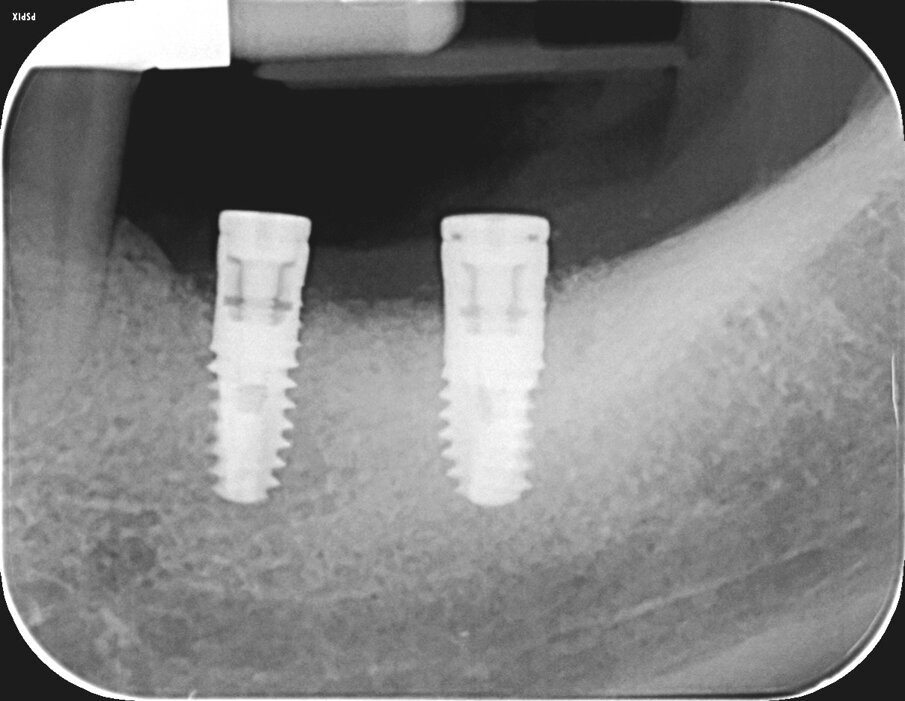

L’innesto è stato protetto con due membrane, opportunamente sagomate e forate per adattarsi attorno a ciascun impianto (Fig. 7). L’operazione è terminata con la sutura dei lembi gengivali tramite filo in poliammide non riassorbibile (Monomyd 4-0, Butterfly, Cavenago) e il posizionamento di due viti di guarigione (Fig. 8). La sutura è stata rimossa a 12 giorni dall’atto chirurgico. Una radiografia di controllo al termine dell’intervento ha confermato l’effettivo ripristino dei volumi ossei perimplantari (Fig. 9). Durante il periodo di guarigione e ai successivi controlli, non si sono osservati segni di sofferenza gengivale (Fig. 10). La paziente non ha lamentato alcuna sintomatologia spontanea o evocata. Al controllo a 3 mesi, l’esame radiografico mostrava il mantenimento dei profili ossei perimplantari (Fig. 11). Sono state quindi rimosse le viti di guarigione e riposizionate le corone.

Al controllo a 15 mesi dall’intervento la paziente non lamenta alcuna sintomatologia e il sanguinamento durante le manovre di igiene orale è scomparso. Eseguita una rx endorale di controllo, si nota un mantenimento ottimale dei livelli ossei e una completa stabilità del contesto perimplantare (Fig. 12).

Fig. 9- Radiografia endorale di controllo al termine dell’intervento.

Fig. 11 - Controllo radiografico a 3 mesi, i livelli perimplantari sono mantenuti.

Fig. 12 - Controllo radiografico a 15 mesi, i livelli perimplantari sono mantenuti.